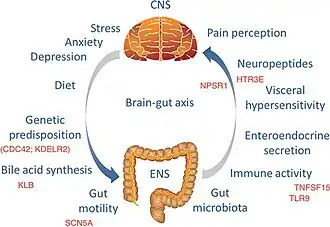

Chronic primary visceral pain

Chronic primary visceral pain occurs in the head or neck viscera of the digestive system; the abdominal area from viscera of the digestive system, such as IBS; the thoracic region, such as non-cardiac chest pain; and the pelvic area from the involvement of viscera of the urinary, digestive, and genital systems, such as chronic pelvic pain.[11] Visceral pain is caused by nociceptor activation in pelvic, thoracic, or abdominal organs.[12]

- Irritable bowel syndrome